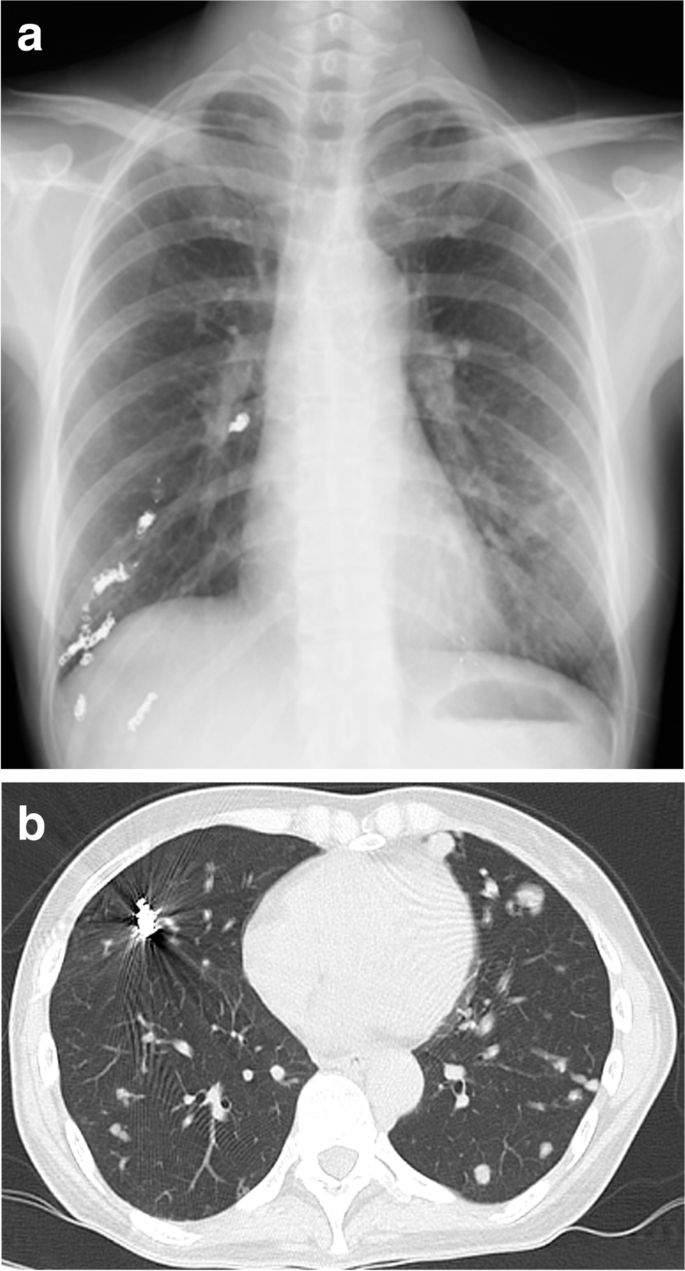

A preoperative physical examination did not reveal any special finding on her body surface. Blood pressure was 105/64 mmHg, with doxazosin at a dose of 3 mg per day, and heart rate was 97 bpm. Peripheral oxygen saturation (SpO2) was 86% in room air, possibly due to the remaining pulmonary AVMs, but the Hugh-Jones classification was class I. Blood tests were remarkable only for hemoglobin level of 11.2 g/dL. Urinary adrenaline, noradrenaline and dopamine levels were 14.2 mcg/day, 965.8 mcg/day and 807.3 mcg/day, respectively. An electrocardiogram (ECG) showed negative T-waves on V3-5 and a transthoracic echocardiogram showed a peripheral left ventricle hypertrophy with an ejection fraction of 67%. Preoperative image examination revealed bilateral pulmonary AVMs (Fig. 1a, b), but no AVM in the brain or in the spinal cord, and a pancreas tail tumor, which was considered to be the origin of the metastatic bone tumor.